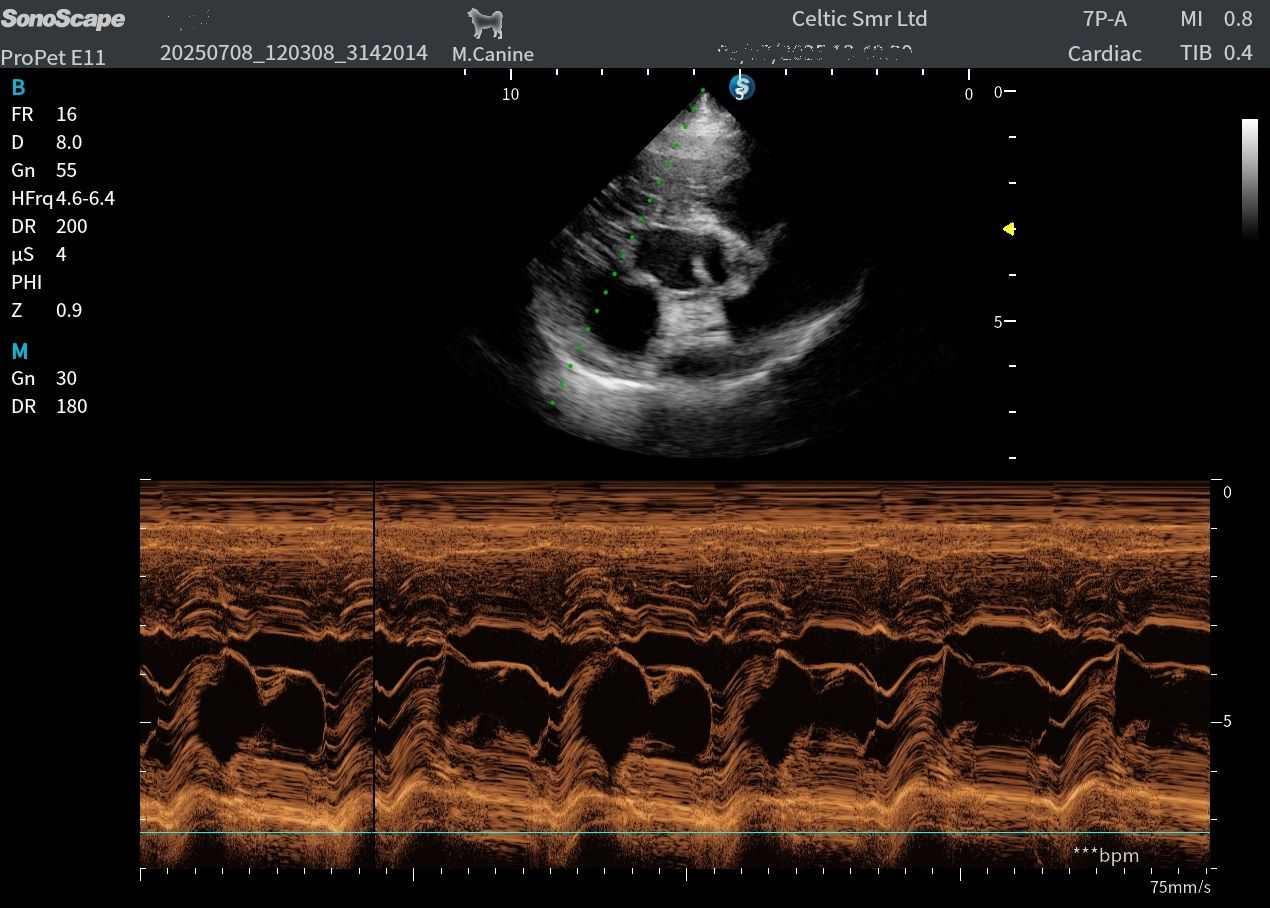

Image quality is one of its absolute highlights. The microconvex and linear probes performed really well for B-mode abdominal scanning, and the microconvex also delivered beautifully clear images in basic cardiac views, so is a great all rounder for the first opinion practice. The phased array probes were equally impressive, producing high-quality heart images suitable for more advanced echo work. For the price point, this machine delivers very good imaging performance.

Images from the ProPet V11